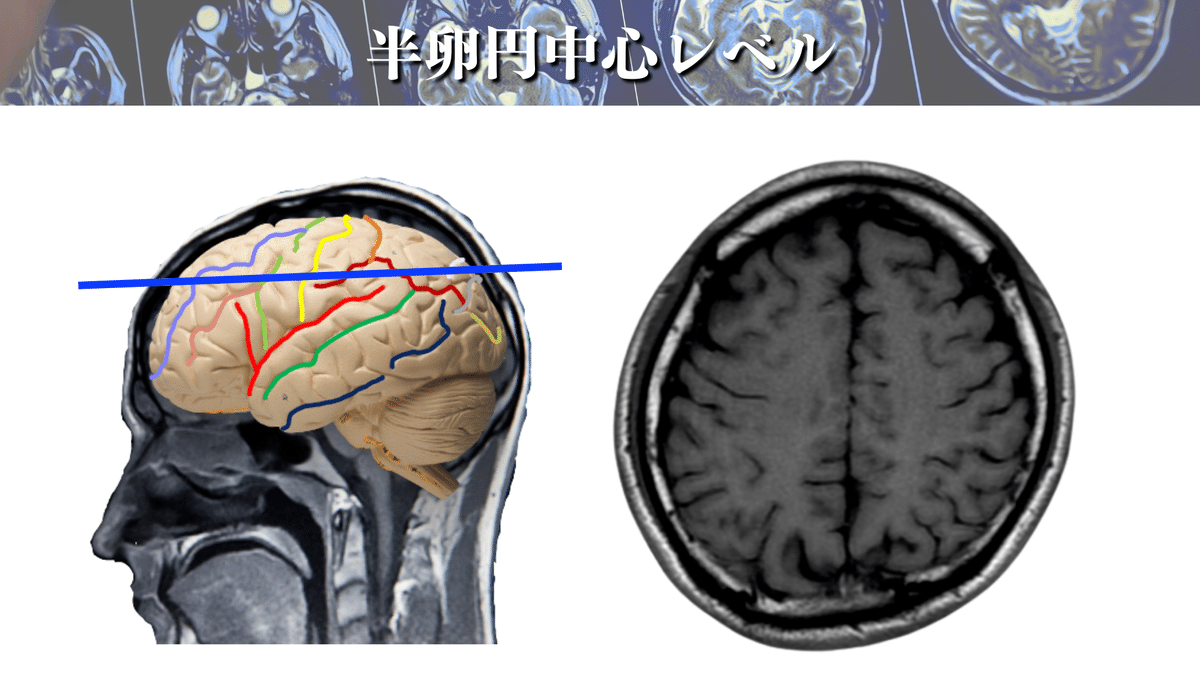

半卵円中心レベル

次はこのレベルです!

上図ではどこをCSTが通るでしょうか?🕵️

では、さっそく解説へいきますね☝️

まずは大まかな場所を押さえましょう!

上図のように大体この辺りをCSTは通過していきます👍